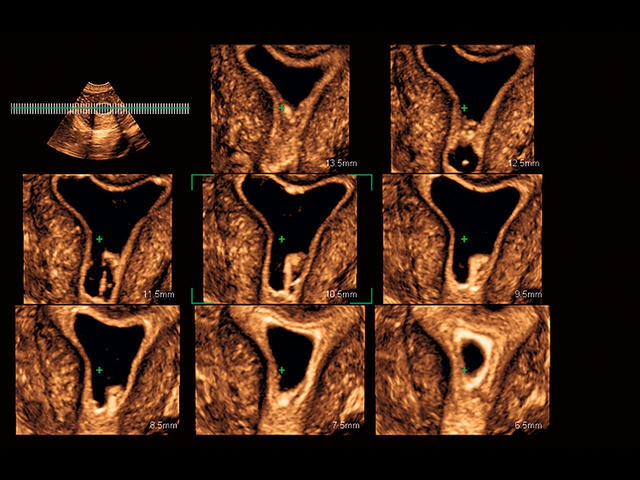

Aplio 500 – ультразвуковой сканер премиум класса, сочетающий в себе быстродействие диагностики и отличное качество визуализации. Более 30 датчиков на выбор, в т.ч. матричные, монокристаллические, 4D, эндоскопические для любых типов исследований. Ультразвуковой сканер позволяет изучать анатомические структуры в высоком разрешении.

Обновленная версия легендарного УЗ-сканера. Стационарный аппарат экспертного класса Aplio 500 Toshiba NEW, визуализирует анатомические структуры в высоком разрешении. Модель позволяет выявить микрокальцификаты, новообразования, нарушения в работе сердца, сосудов и мышц. Присутствует функция виртуальной эндоскопии, 4D-сканирования, эластометрии тканей, УЗИ с контрастированием. За повышение качества изображения отвечают технологии ApliPure и Superb Microvascular Imaging. Первая задействует возможности пространственного и частотного кодирования, формирует цельный визуальный ряд с сохранением клинических маркеров. Вторая улучшает отображение микрососудистого русла, используя доплеровский эффект. Модель оснащена 21-дюймовым монитором, имеет 4 активных порта. Возможно подключение педиатрических, интраоперационных, лапароскопических и чреспищеводных датчиков.

• Fly Thru. Виртуальная эндосонография обеспечивает построение трехмерной модели полостей, протоков и сосудов в рельном времени, облегчает организацию инвазивных процедур и динамических исследований. Посредством Fly Thru можно установить шунты и стенты, проводить точные оперативные вмешательства.